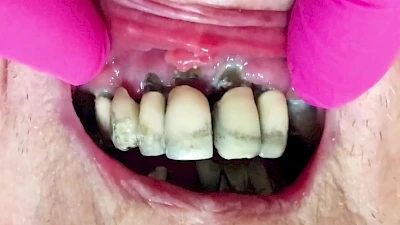

Eine geringe spürbare Beweglichkeit der Zähne ist durchaus normal, da Zähne über Fasern im Kieferknochen aufgehängt sind. Lassen sich Zähne, Kronen oder Brücken jedoch deutlich sichtbar bewegen, besteht die Gefahr, dass sie sich lösen und verschluckt oder aspiriert werden. Deshalb sollte in diesen Fällen der Zahnarzt verständigt werden.